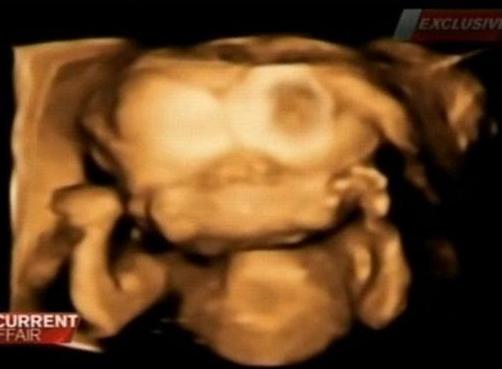

INCREDIBIL! A crezut că are gemeni dar ecografia a ÎNGROZIT-O

În Australia, doi tineri păriţi au fost extreme de bucuroşi după ce medicii le-au spus că vor avea gemeni. Fericirea nu a ţinut însă mult. La un control de rutină au aflat că au un singur copil cu o malformaţie oribilă.

După o ecografie obişnuită, cei doi au aflat că era vorba de fapt de un singur făt, care avea două capete conectate la acelaşi trunchi cerebral.